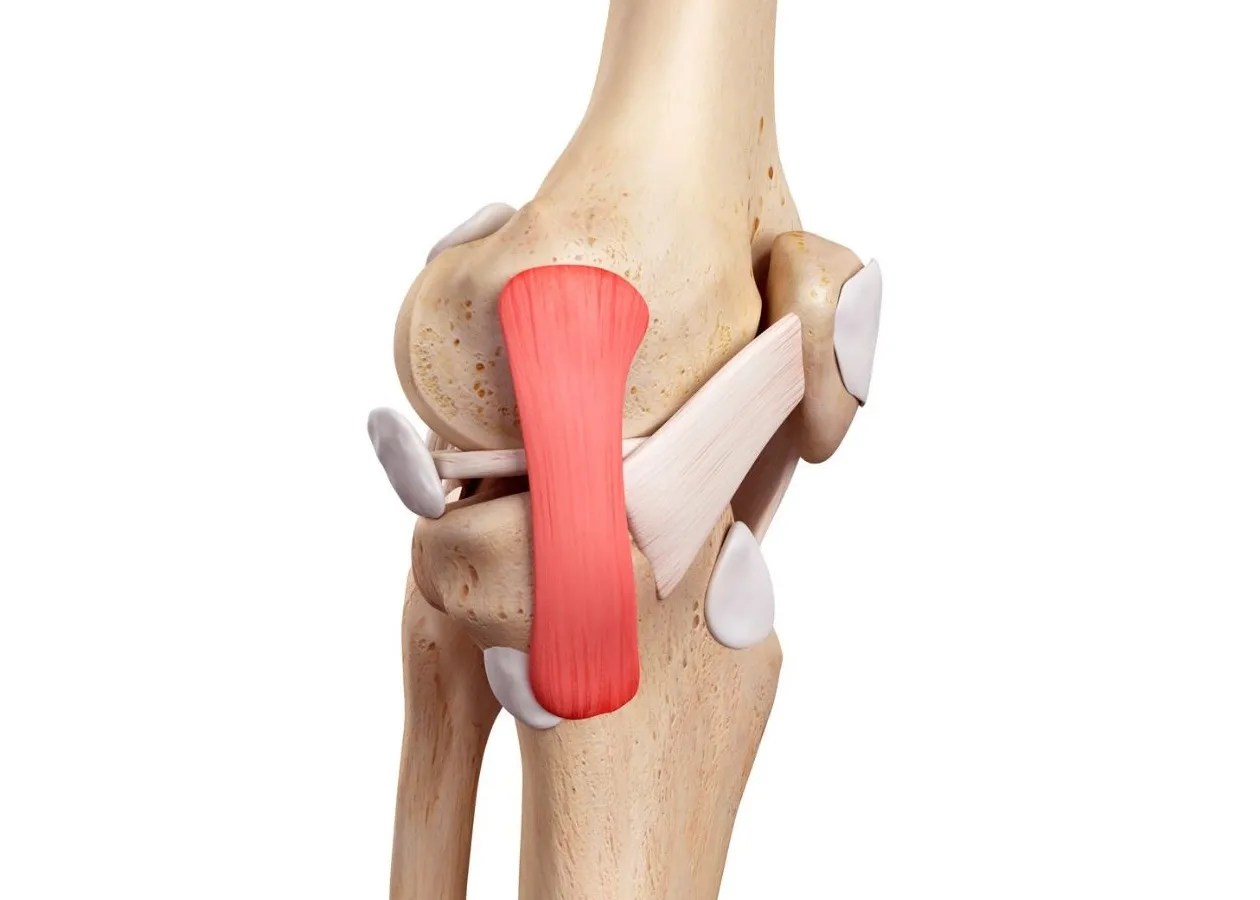

La tendinitis del ligamento colateral medial es una inflamación o irritación del ligamento colateral medial (LCM).

Este ligamento se encuentra en la parte interna de la rodilla y cumple una función muy importante: estabilizarla y evitar que se desplace lateralmente.

La fisioterapia juega un papel clave en la recuperación.

Un fisioterapeuta te guiará a través de ejercicios diseñados para fortalecer los músculos que rodean la rodilla, mejorando la estabilidad y reduciendo el estrés sobre el ligamento.